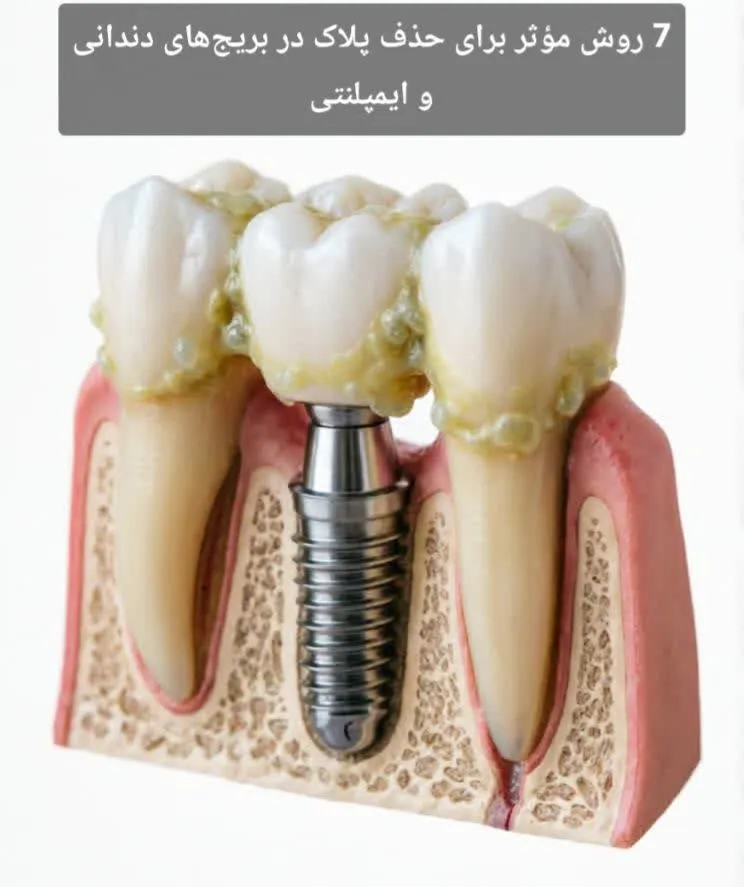

بریجهای دندانی و روکشهای ایمپلنتی از پرکاربردترین روشهای جایگزینی دندانهای از دسترفته هستند. این درمانها علاوه بر بازگرداندن عملکرد جویدن و زیبایی لبخند، به حفظ تعادل اکلوژن و جلوگیری از جابهجایی دندانها کمک میکنند. با این حال، موفقیت بلندمدت آنها وابسته به یک عامل کلیدی است: حذف پلاک در بریجهای دندانی و ایمپلنتی بهصورت منظم و اصولی.

پلاک میکروبی یک لایه بیوفیلم چسبنده حاوی باکتریهاست که در صورت عدم پاکسازی، میتواند منجر به پوسیدگی دندانهای پایه بریج، التهاب لثه، بوی بد دهان و حتی شکست درمان شود. در ایمپلنتها نیز تجمع پلاک ممکن است به پریایمپلنتایتیس و تحلیل استخوان منجر گردد. در این مقاله بهصورت کاملاً تخصصی به بررسی روشهای مؤثر، ابزارهای مناسب، تکنیکهای صحیح و اشتباهات رایج در حذف پلاک در بریجهای دندانی و ایمپلنتی میپردازیم.

چرا پلاک در بریجها بیشتر تجمع مییابد؟

بریجهای دندانی دارای ساختاری هستند که شامل:

- دندانهای پایه (اباتمنت)

- پونتیک (دندان جایگزین معلق)

- ناحیه تماس با لثه

میباشند. زیر پونتیک فضایی وجود دارد که مستعد تجمع مواد غذایی و باکتریهاست. از آنجا که مسواک بهتنهایی نمیتواند این ناحیه را بهطور کامل تمیز کند، احتمال باقی ماندن پلاک افزایش مییابد.

در ایمپلنتها نیز ناحیه اتصال روکش به اباتمنت و خط لثه اطراف آن، محل شایع تجمع بیوفیلم است.